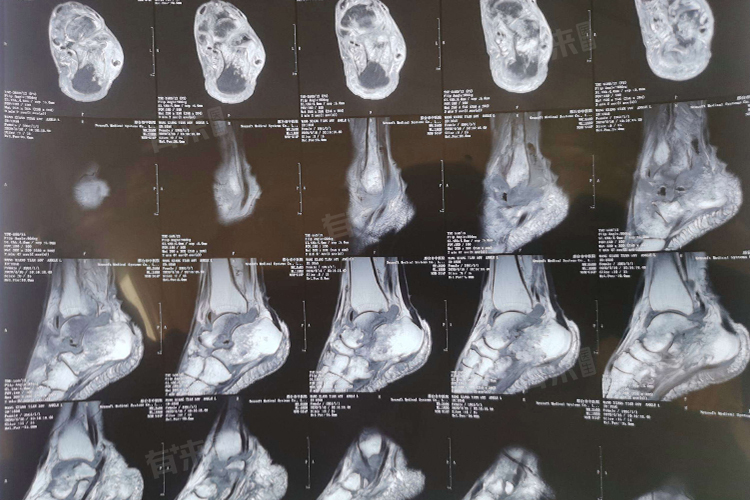

- 高场强设备能更清晰地显示脚踝关节的细微结构,包括韧带、肌腱、软骨等,有助于发现微小病变,但设备成本和运行维护费用高,检查价格通常在600-1000元。超高场强设备虽然成像质量更优,但使用相对较少,费用也更高。

- 为全面评估脚踝状况,医生会根据病情需求选择不同的扫描序列。单一序列检查价格相对较低,若同时采用多个序列进行扫描,能够更准确地判断病变性质、范围,不过费用也会随之增加。

- 脚踝核磁共振检查可分为局部扫描和全踝关节扫描,局部扫描针对特定区域,如怀疑某条韧带损伤时,仅对该韧带所在部位进行扫描,费用相对较低;全踝关节扫描则涵盖整个踝关节及其周围结构,能更全面地评估踝关节整体状况,收费自然更高。此外,若需要对双侧脚踝同时进行检查,费用也会相应增加。